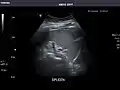

Ultrasound can also be used if there is suspicion of enlargement of one or more organs, such as used in screening for abdominal aortic aneurysm, investigation for splenomegaly or urinary retention.

In cases of infectious mononucleosis, splenomegaly is a common symptom, and health care providers may consider using abdominal ultrasonography to get insight into a person's condition.[5] However, because spleen size varies greatly, ultrasonography is not a valid technique for assessing spleen enlargement and should not be used in typical circumstances or to make routine decisions about fitness for playing sports.[5]

Spleen: Normal in size.